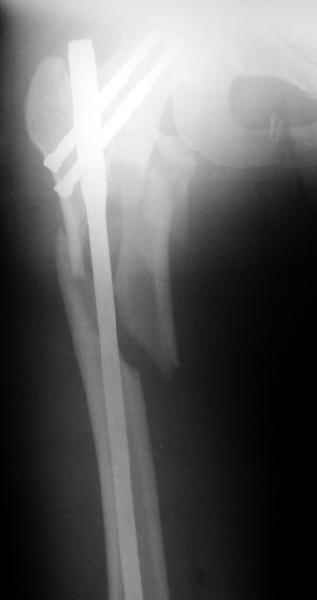

a> Диагноз Закрытый оскольчатый подвертельный перелом правой

a> бедренной кости со смещением отломков,

a> оскольчатый перелом большого вертела, отрывной перелом малого вертела.

Наверно, можно и так сказать, но можно и тоже самое - 4-фрагментный вертельный перелом. Выбор тот же, но с учетом молодого возраста реконструкционный гвоздь тут более применим. Вот уже наш пример.